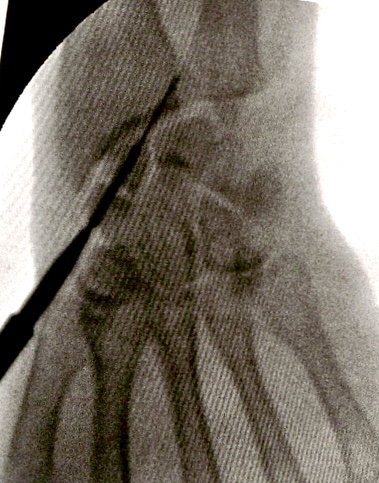

xx 男 36岁 腕舟骨骨折 掌侧切开复位内固定术 。

术前X片显示舟骨腰部骨折

术前X片显示舟骨腰部骨折,AO分型B2型。

掌侧入路

Herbert钉固定